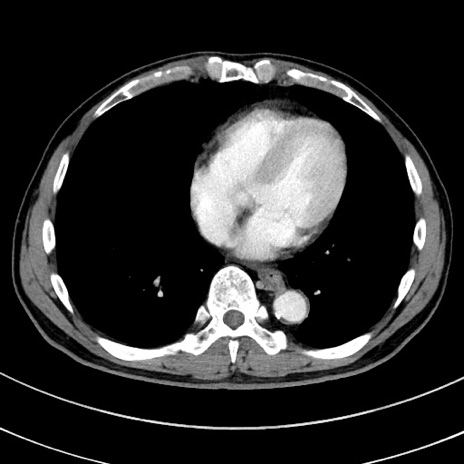

症例8(横断像)

【症例】 60歳代男性

【主訴】 黒色吐物

【現病歴】 4日前から嘔気自覚、2日前の朝食後にも嘔気あり、自分で手で嘔吐反射起こし嘔吐したところ血が混ざっていたため受診。

【既往歴】 5年前汎発性腹膜炎を伴う急性虫垂炎で手術、高血圧、前立腺肥大症、高脂血症

【身体所見】 腹部正中に手術癩痕あり 腹部平坦・軟圧痛なし膨満感あり

【データ】WBC 8400、CRP 4.54